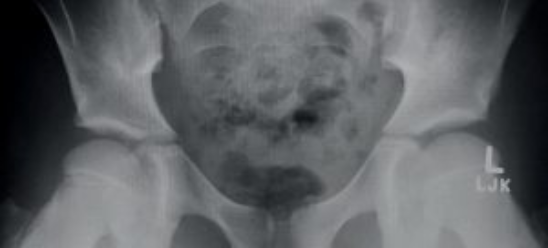

The following images are from a young dancer, now 14, who had started experiencing hip pain at the age of 10. X-rays were taken and they were told that there was nothing wrong. (Her teacher told her it was normal to have hip pain..!) She continued to have hip issues and had X-rays retaken again at ages 13 and again at 14 before she saw me.

Look carefully at the images below, and you can see that the shape of the hip socket has actually shifted due to the aggressive stretching that she was doing at her dance school. This has now calcified and so will remain this way for the rest of her life.

She was still complaining of hip pain at 13, so more X rays were ordered. It is easy to see the damage in the hip socket in the following images. The black line indicates major issues with the surface of the hip socket and there is evidence of excessive movement across both of the growth plates of the femur. The head of the femur is no longer nicely rounded and has been flattened due to excessive loading.

At 14, the student was still complaining of sore hips, so another set of images were taken. She was also told by a friend to come and see us at Perfect Form Physio for treatment for her ongoing hip pain.

In these images the pelvis has begun to fuse (as it should), however the head of the femur (thigh bone) is flattened and the shape of the socket is shallow. There is also development of a "pincer type deformity" at the top of the hip socket that was not present in previous x-rays that will contribute to anterior hip impingement. Bone develops in response to load, so it is probable that this developed in response to repeated compression after kicking her right leg up repeatedly...